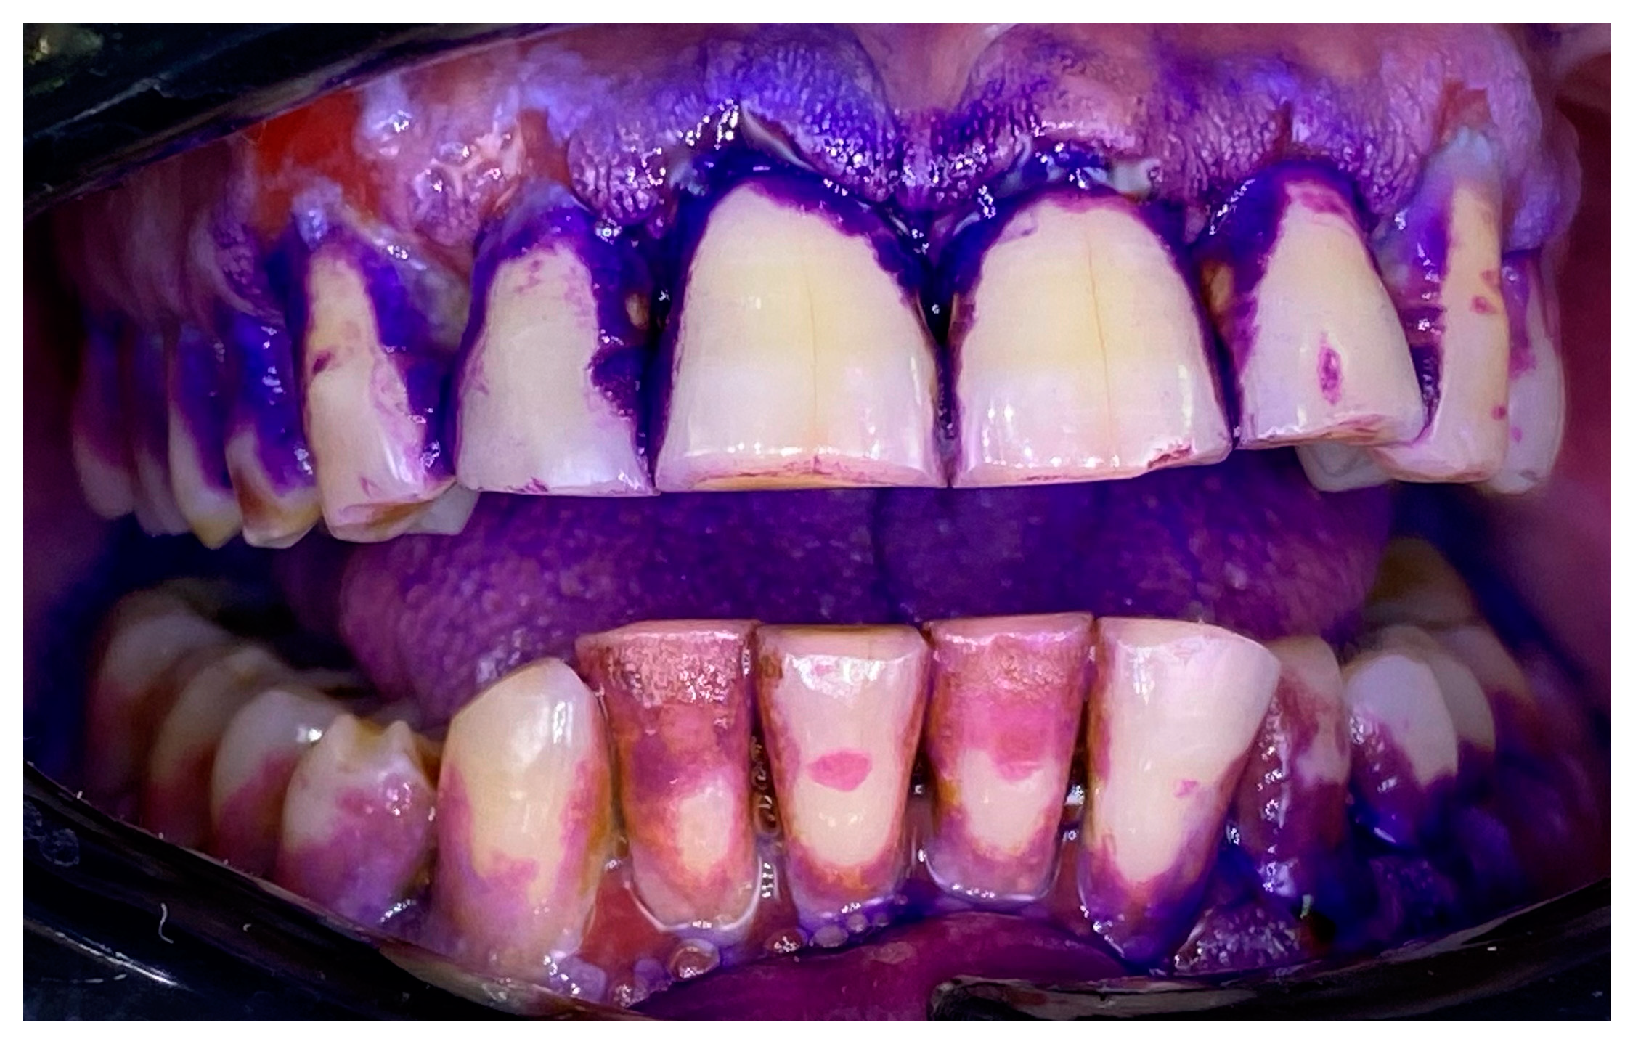

2.1. Clinical Case 1—Mucous Membrane Pemphigoid (MMP)

2.2. Clinical Case 2—Pemphigus Vulgaris (PV)

2.3. Clinical Case 3—Oral Lichen Planus (OLP)